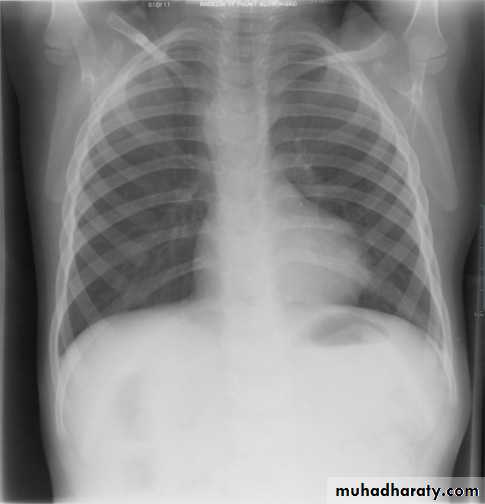

Tetralogy of Fallot (TOF) is one of the most common cyanotic congenital heart conditions and continues to be a major source of morbidity .

Tetralogy of Fallot is classically characterized by four features which are:

ventricular septal defect (VSD) 6

right ventricular outflow tract obstruction (RVOTO) due to: pulmonary artery stenosis

overriding aorta

right ventricular hypertrophy

Radiographic features

Plain film "boot shaped" heart ( TOF )

Plain films may classically show :

1. "boot shaped" heart with an upturned cardiac apex due to right ventricular hypertrophy and concave pulmonary arterial segment.

2.Pulmonary oligaemia due to decreased pulmonary arterial flow.

3.Right sided aortic arch is seen in 25%.

TOF